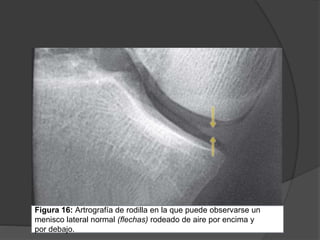

Figura 16: Artrografía de rodilla en la que puede observarse un

menisco lateral normal (flechas) rodeado de aire por encima y

por debajo.

Figura 16: Artrografíade rodilla en la que puede observarse un menisco lateral normal (flechas) rodeado de aire por encima y por debajo.